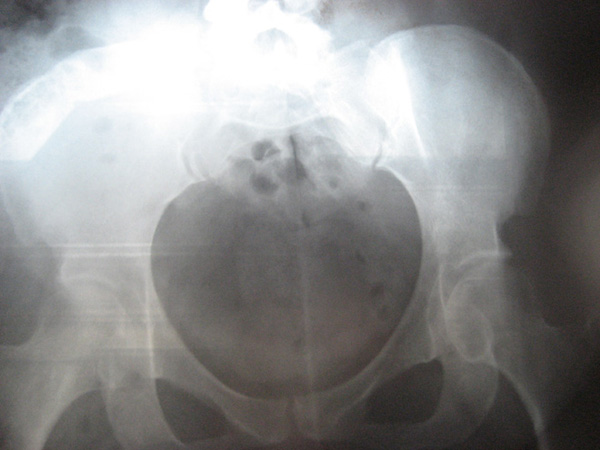

Cas clinique N°40

Dr Véra Lemaire Paris

Il s'agit d'une patiente âgée de 45 ans, secrétaire de direction, qui souffre de sa hanche droite depuis 2-3 ans. La douleur s'aggrave progressivement.

A l'examen de cette patiente obèse (1m60, 88,4kgs), la mobilité de la hanche droite, qui est douloureuse, est discrètement limitée.